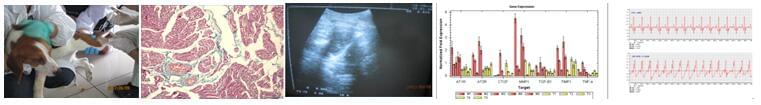

安必奇为您提供6大类心脑血管疾病药理学实验,包括缺血性心脏病、心律失常、厥脱症、高脂血症、高血压、动脉粥样硬化。成功案例:实验目的:犬心房颤动治疗实验方案:比格犬房颤模型+心电图检测+形态学染色(Masson染色)+超声波探测诊断+RT-PCR检测实验结果: